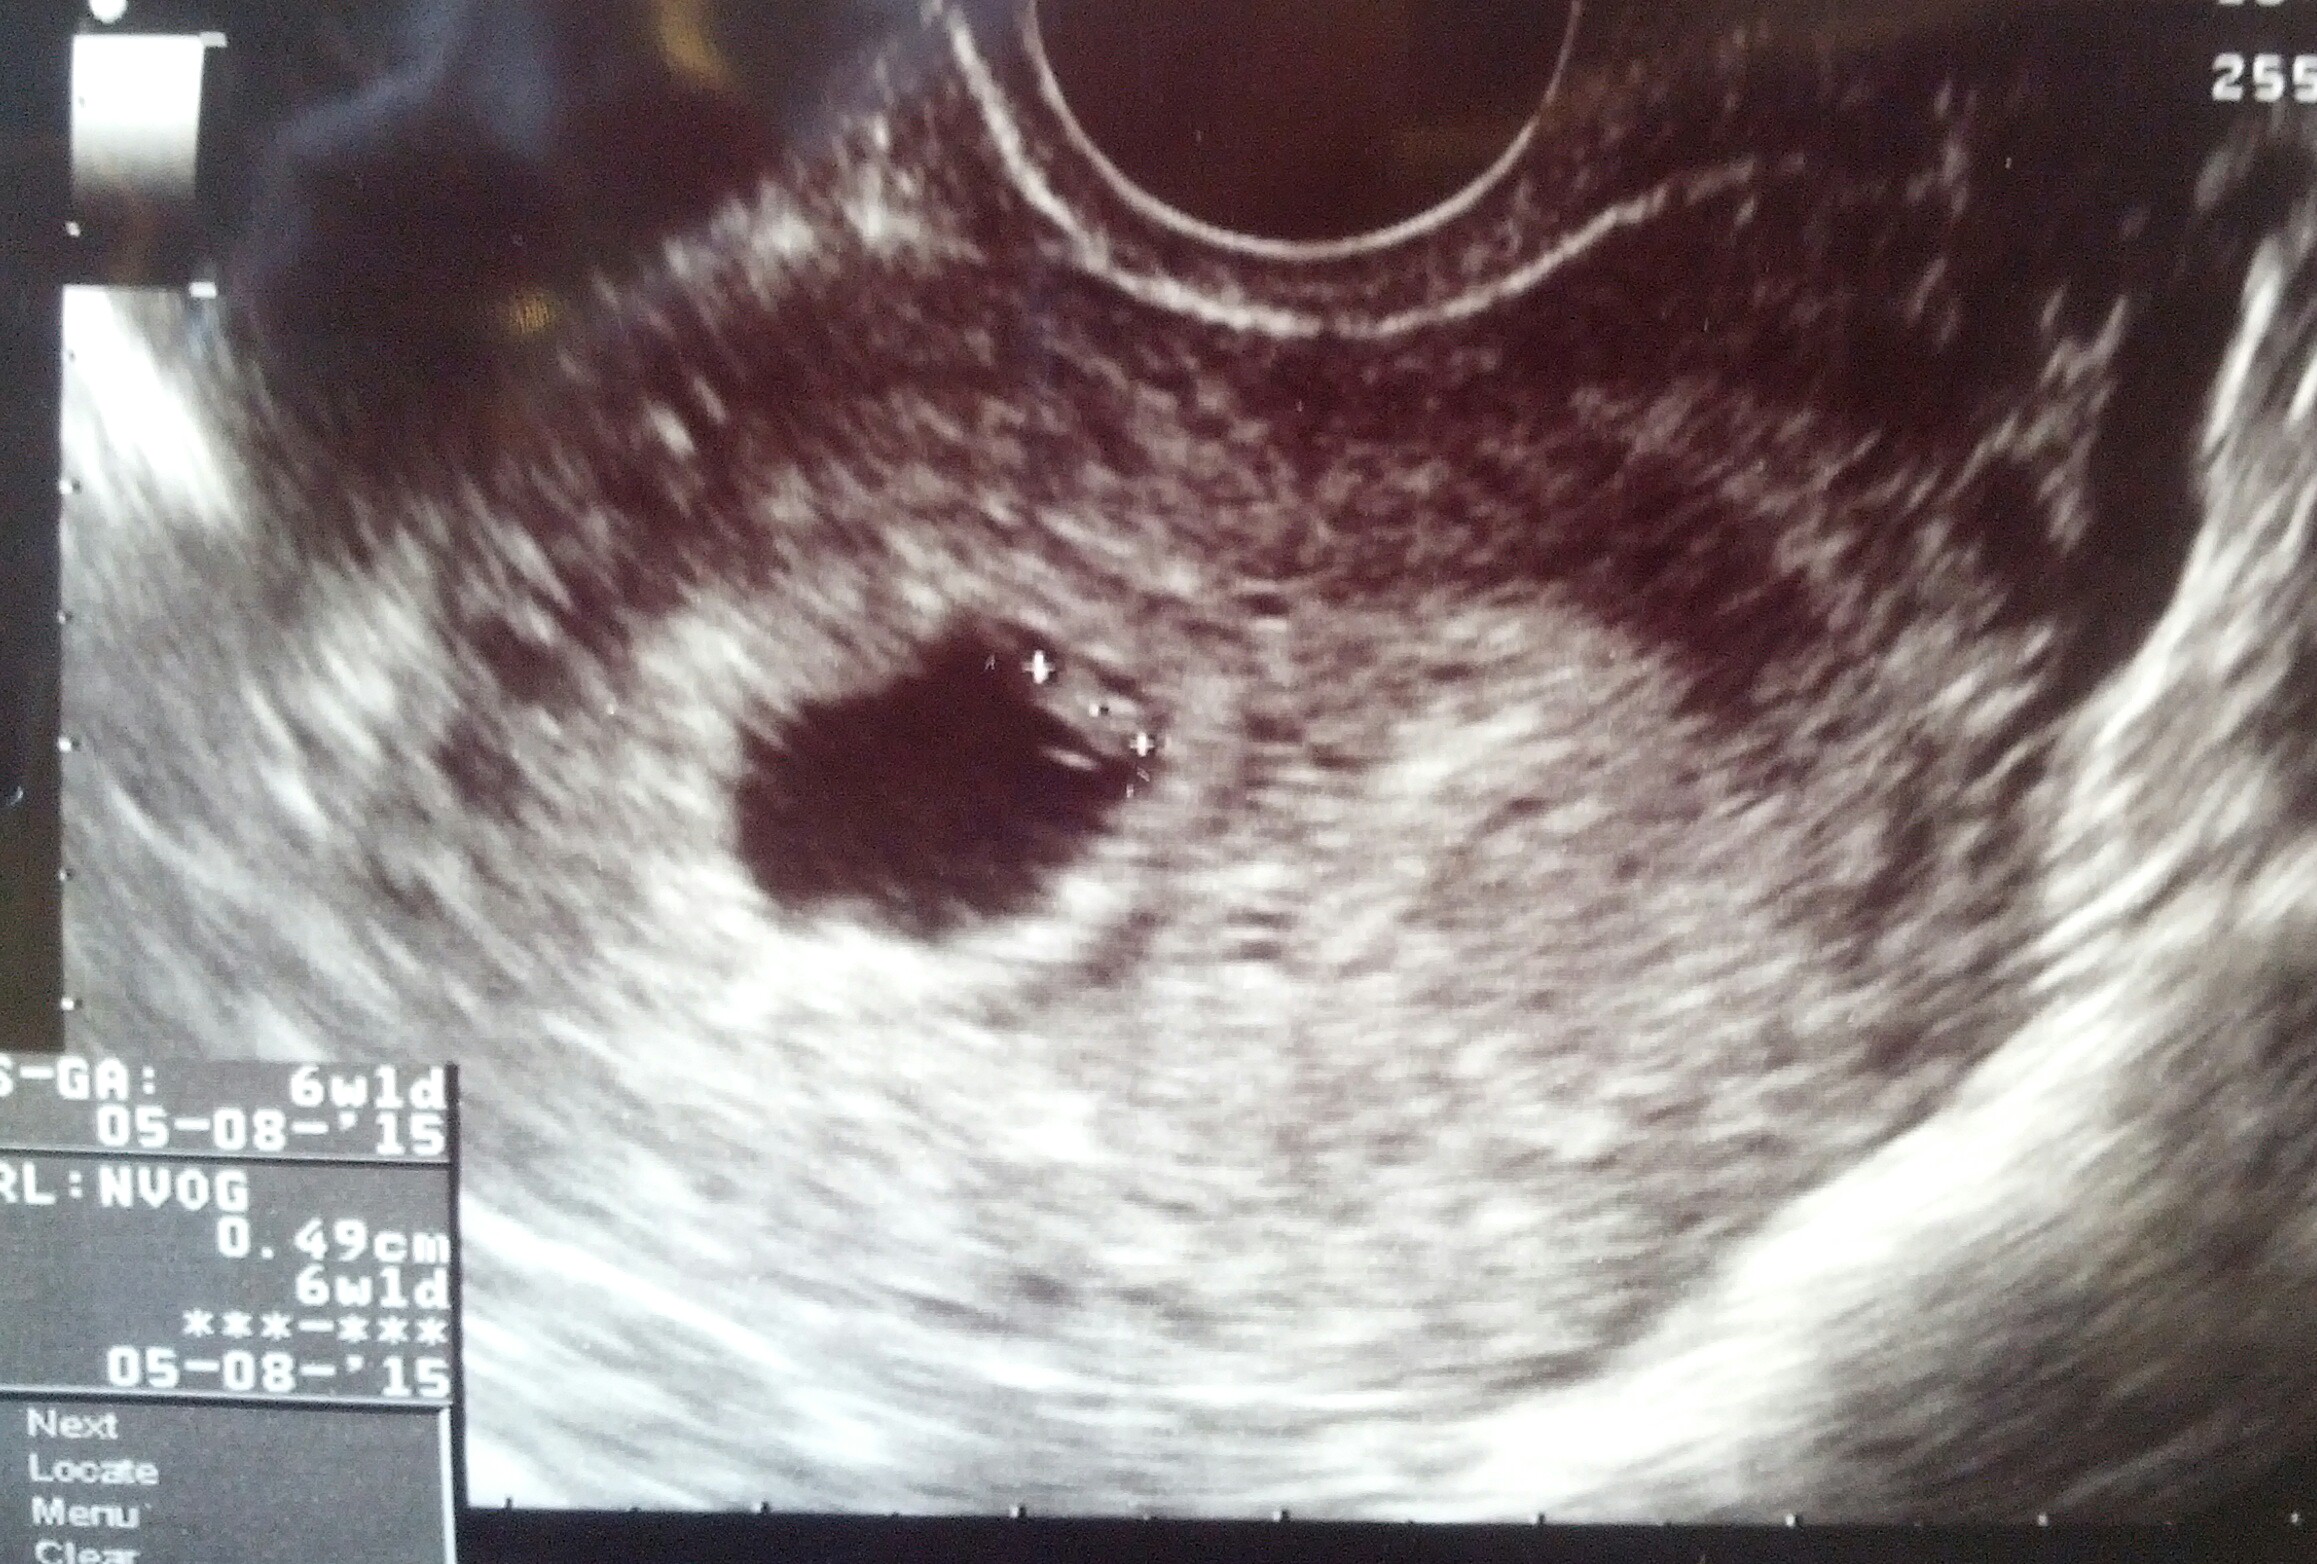

Hi ladies, had a scan today at 6 weeks

Scan: transvaginal

Plane: sagital

Orientation: my right side is on the right and my left side is on the left of the picture.

Any one who is comfortable to help explain your guess.